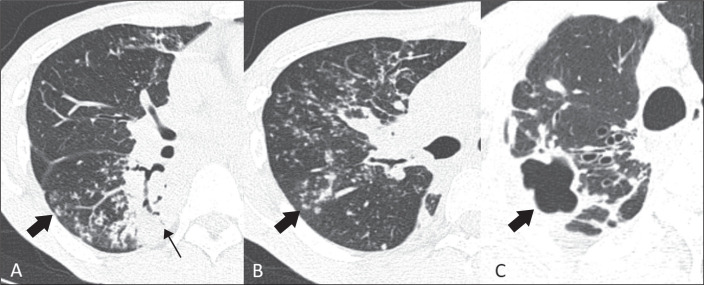

Results: Among the patients with a confirmed diagnosis of PTB, small pulmonary nodules with a peribronchovascular distribution were significantly more common in the patients with a positive sputum smear microscopy result (47.4% vs. 8.3%; p = 0.046), as were a miliary pattern (36.8% vs. 0.0%; p = 0.026), septal thickening (84.2% vs. 41.7%; p = 0.021), and lymph node enlargement (52.6% vs. 8.3%; p = 0.020). Small pulmonary nodules with a centrilobular distribution were significantly more common among the culture-positive patients (75.0% vs. 35.7%; p = 0.045), as was a tree-in-bud pattern (91.7% vs. 42.9%; p = 0.014). A tree-in-bud pattern, one of the main tomography findings characteristic of PTB, had a sensitivity, specificity, positive predictive value, and negative predictive value of 71.0%, 73.1%, 75.9%, and 67.9%, respectively.